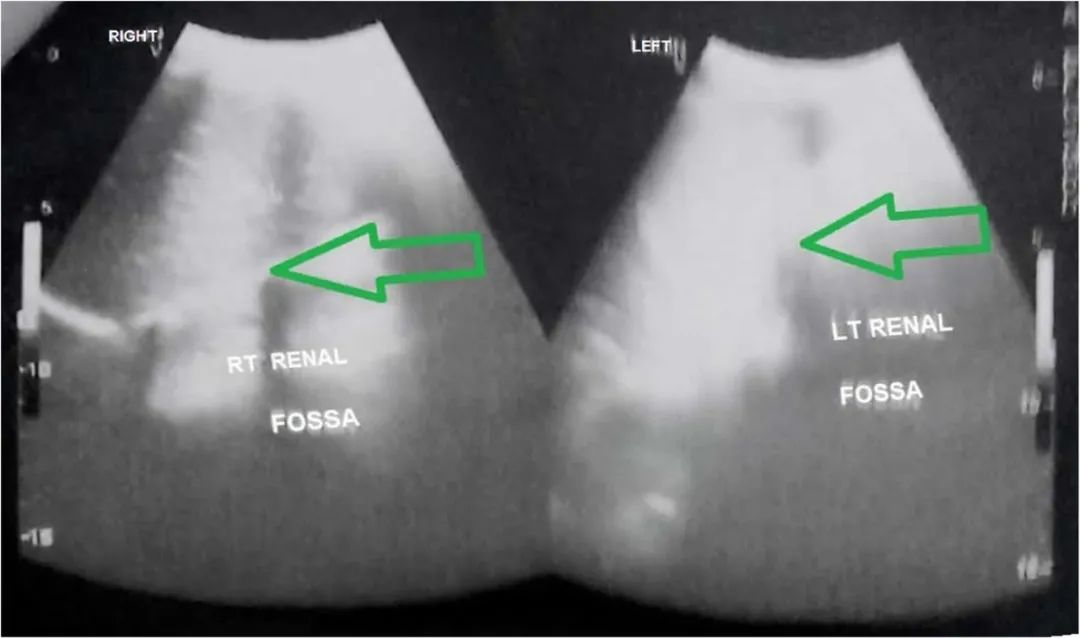

腹部的超声:肾窝空虚。